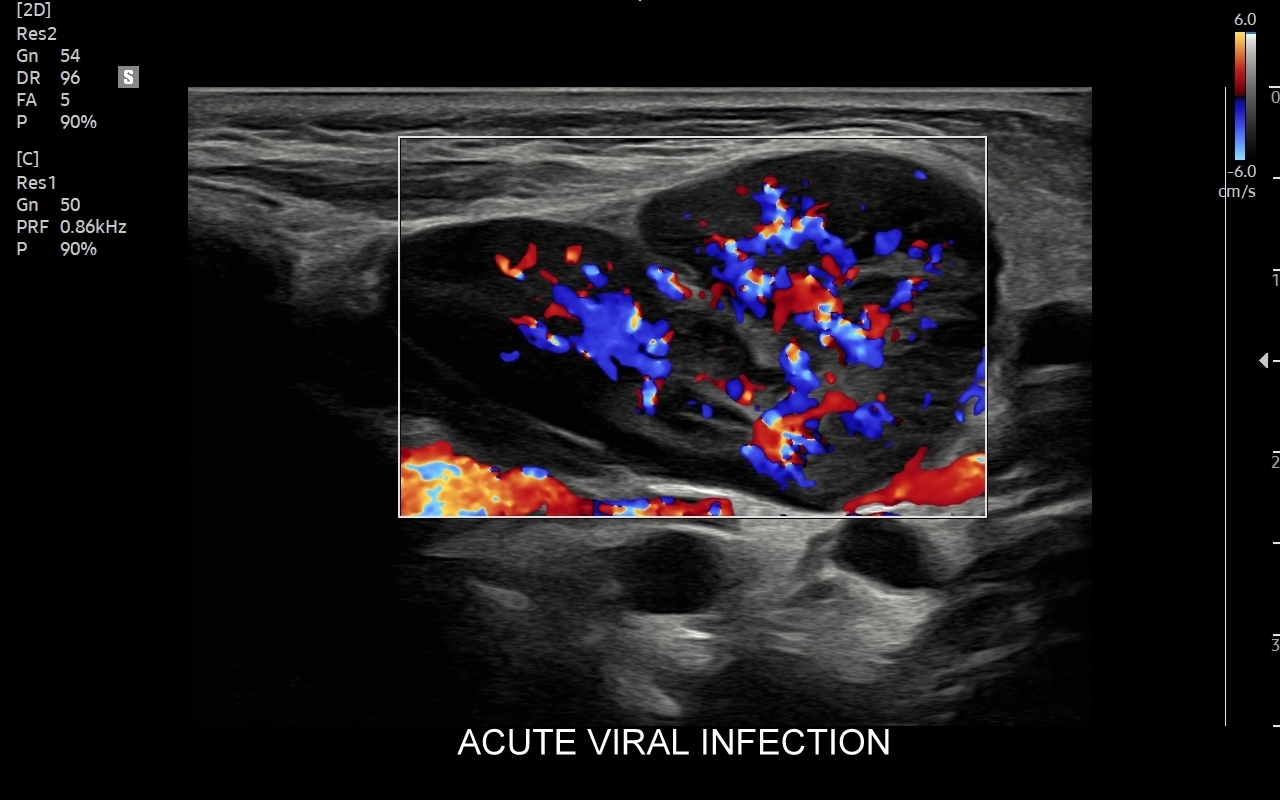

W przebiegu chorób, w których dochodzi do stymulacji układu odpornościowego, węzły limfatyczne ulegają powiększeniu. Przykładami są miejscowe lub uogólnione procesy zapalne i autoimmunologiczne, schorzenia infekcyjne bakteryjne, wirusowe, grzybicze i pasożytnicze. Węzły chłonne powiększać się mogą również w przebiegu białaczek i chłoniaków, a także w trakcie chorób nowotworowych, w których dochodzi do tworzenia przerzutów.

Badanie USG jest podstawową metodą obrazowania węzłów chłonnych. W jego trakcie ocenia się nie tylko wielkość węzłów, lecz także ich kształt, proporcje wymiarów, morfologię, czyli wygląd zewnętrzny oraz strukturę wewnętrzną, ich unaczynienie, spoistość, a także tkanki otoczające. W trakcie interpretacji badania pod uwagę bierze się również zbierany od pacjenta wywiad chorobowy oraz wyniki innych badań obrazowych i laboratoryjnych takich jak morfologia, OB, CRP, żelazo, ferrytyna, TIBC, innych parametrów infekcyjnych, a także onkologicznych. Ultrasonografia węzłów chłonnych jest procedurą bezpieczną i dokładną. W Pracowni dr Szczepańskiego węzły chłonne oceniane są nowoczesną metodą MPUS (multiparametryczne badanie USG), w szczególności z zastosowaniem trybów mikrounaczynienia i elastografii.

Do powiększenia węzłów chłonnych szyi, stanu określanego jako limfadenopatia, dochodzi najczęściej w przebiegu chorób zakaźnych górnych dróg oddechowych, wirusowych i bakteryjnych. Inne przykłady przyczyn limfadenopatii szyjnej obejmują ropne choroby zębów, migdałków i zatok przynosowych; odczyny w chorobach autoimmunologicznych, np. w chorobie Hashimoto i Sjögrena; a także rozrostowe schorzenia układu hematologicznego (białaczki i chłoniaki) i choroby nowotworowe jak np. rak tarczycy, krtani, migdałka, czy języka. Należy mieć na uwadze, iż w przypadku podejrzenia chorób układu krwiotwórczego oraz mononukleozy zakaźnej, oprócz węzłów chłonnych, niezbędne jest również badanie USG wątroby i śledziony. W części przypadków, gdy podejrzewa się możliwość choroby nowotworowej lub w celu jej wykluczenia, lekarz może zalecić rozszerzenie diagnostyki obrazowej na inne obszary ciała.